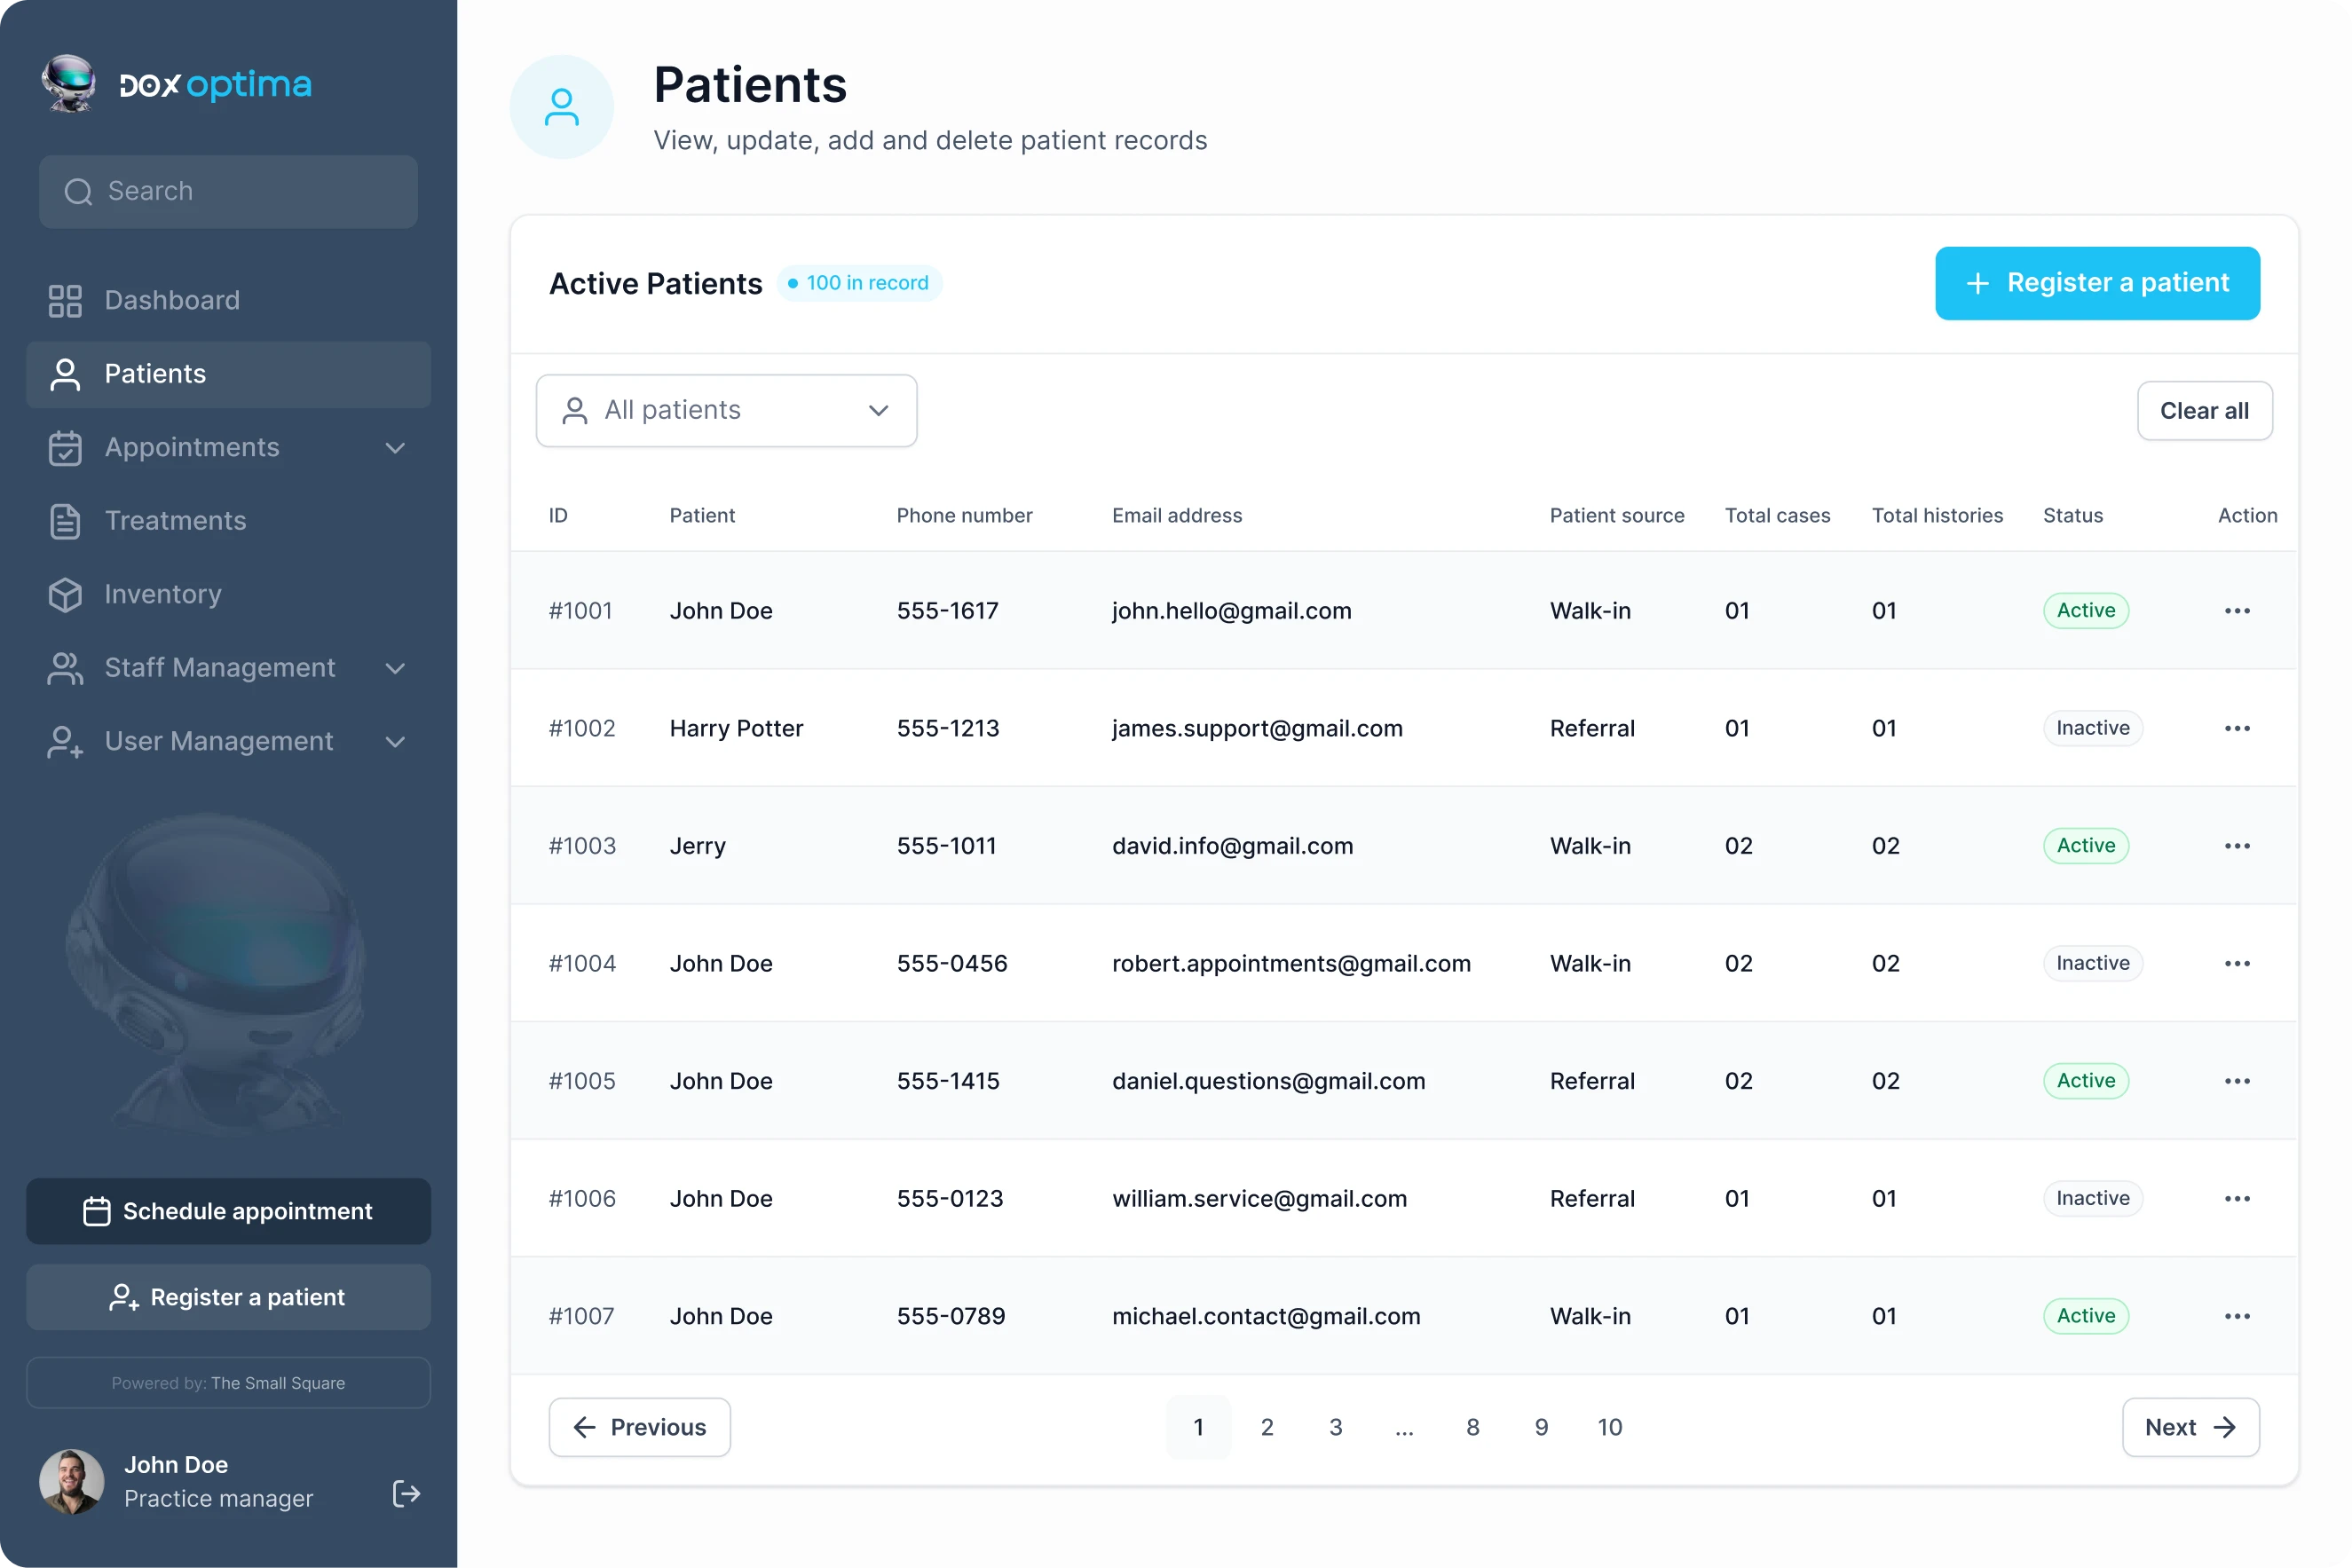

Streamline Your Workflow

Easily manage your clinic with a centralized system that automates tasks, updates schedules, and provides insights, so you can focus on patient care.

DoxOptima streamlines clinic operations with automated workflows, intuitive tools, and real-time insights, simplifying appointments, patient records, staff management, and finances for enhanced efficiency